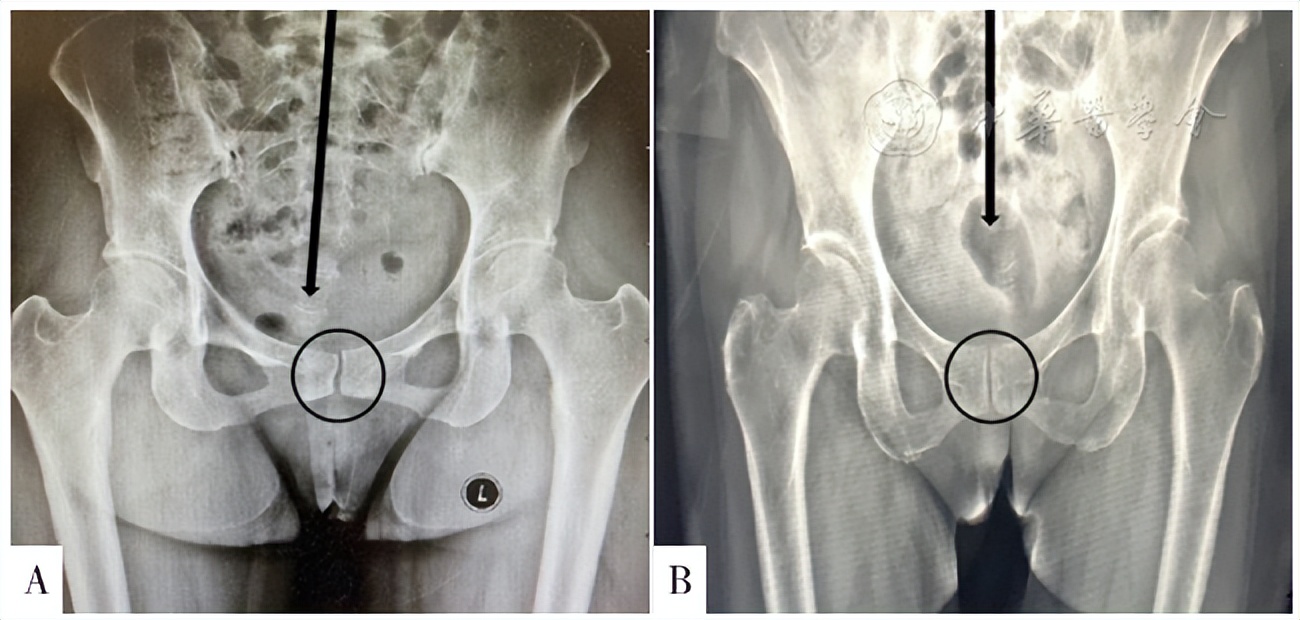

查体结果:(1)平卧时患者左腿比右腿长约1 cm(比较双侧的内踝高度);(2)左侧髂前上棘高于右侧髂前上棘;(3)左侧髂嵴高于右侧髂嵴;(4)左侧髂后上棘低于右侧髂后上棘;(5)双侧骶髂关节区深压痛,右侧重于左侧;(6)耻骨联合区压痛;(7)其他检查阴性。行骨盆X线检查,结果见图2A。

图2 病例骨盆平片检查结果注:A为治疗前,圆圈示双侧耻骨不在同一水平,箭头示骶尾骨向右侧倾斜(提示骨盆旋移);B为治疗后,圆圈示双侧耻骨恢复到同一水平,箭头示骶尾骨恢复居中位置(骨盆旋移纠正) Figure 2 X-ray results of the pelvis |

综合分析症状、病史、查体及辅助检查结果,考虑患者是1例由于骶髂关节紊乱导致骨盆旋移进而诱发PGAD/GPD的特殊病例。明确诊断后,采用DPS对患者进行骶髂关节复位,疗效明显:首次治疗后,患者症状即减轻90%左右;后经4次骶髂关节和骨盆调整(每次间隔3 d)并辅以理疗和相应康复训练,患者症状完全消失。骨盆平片复查结果见图2B。